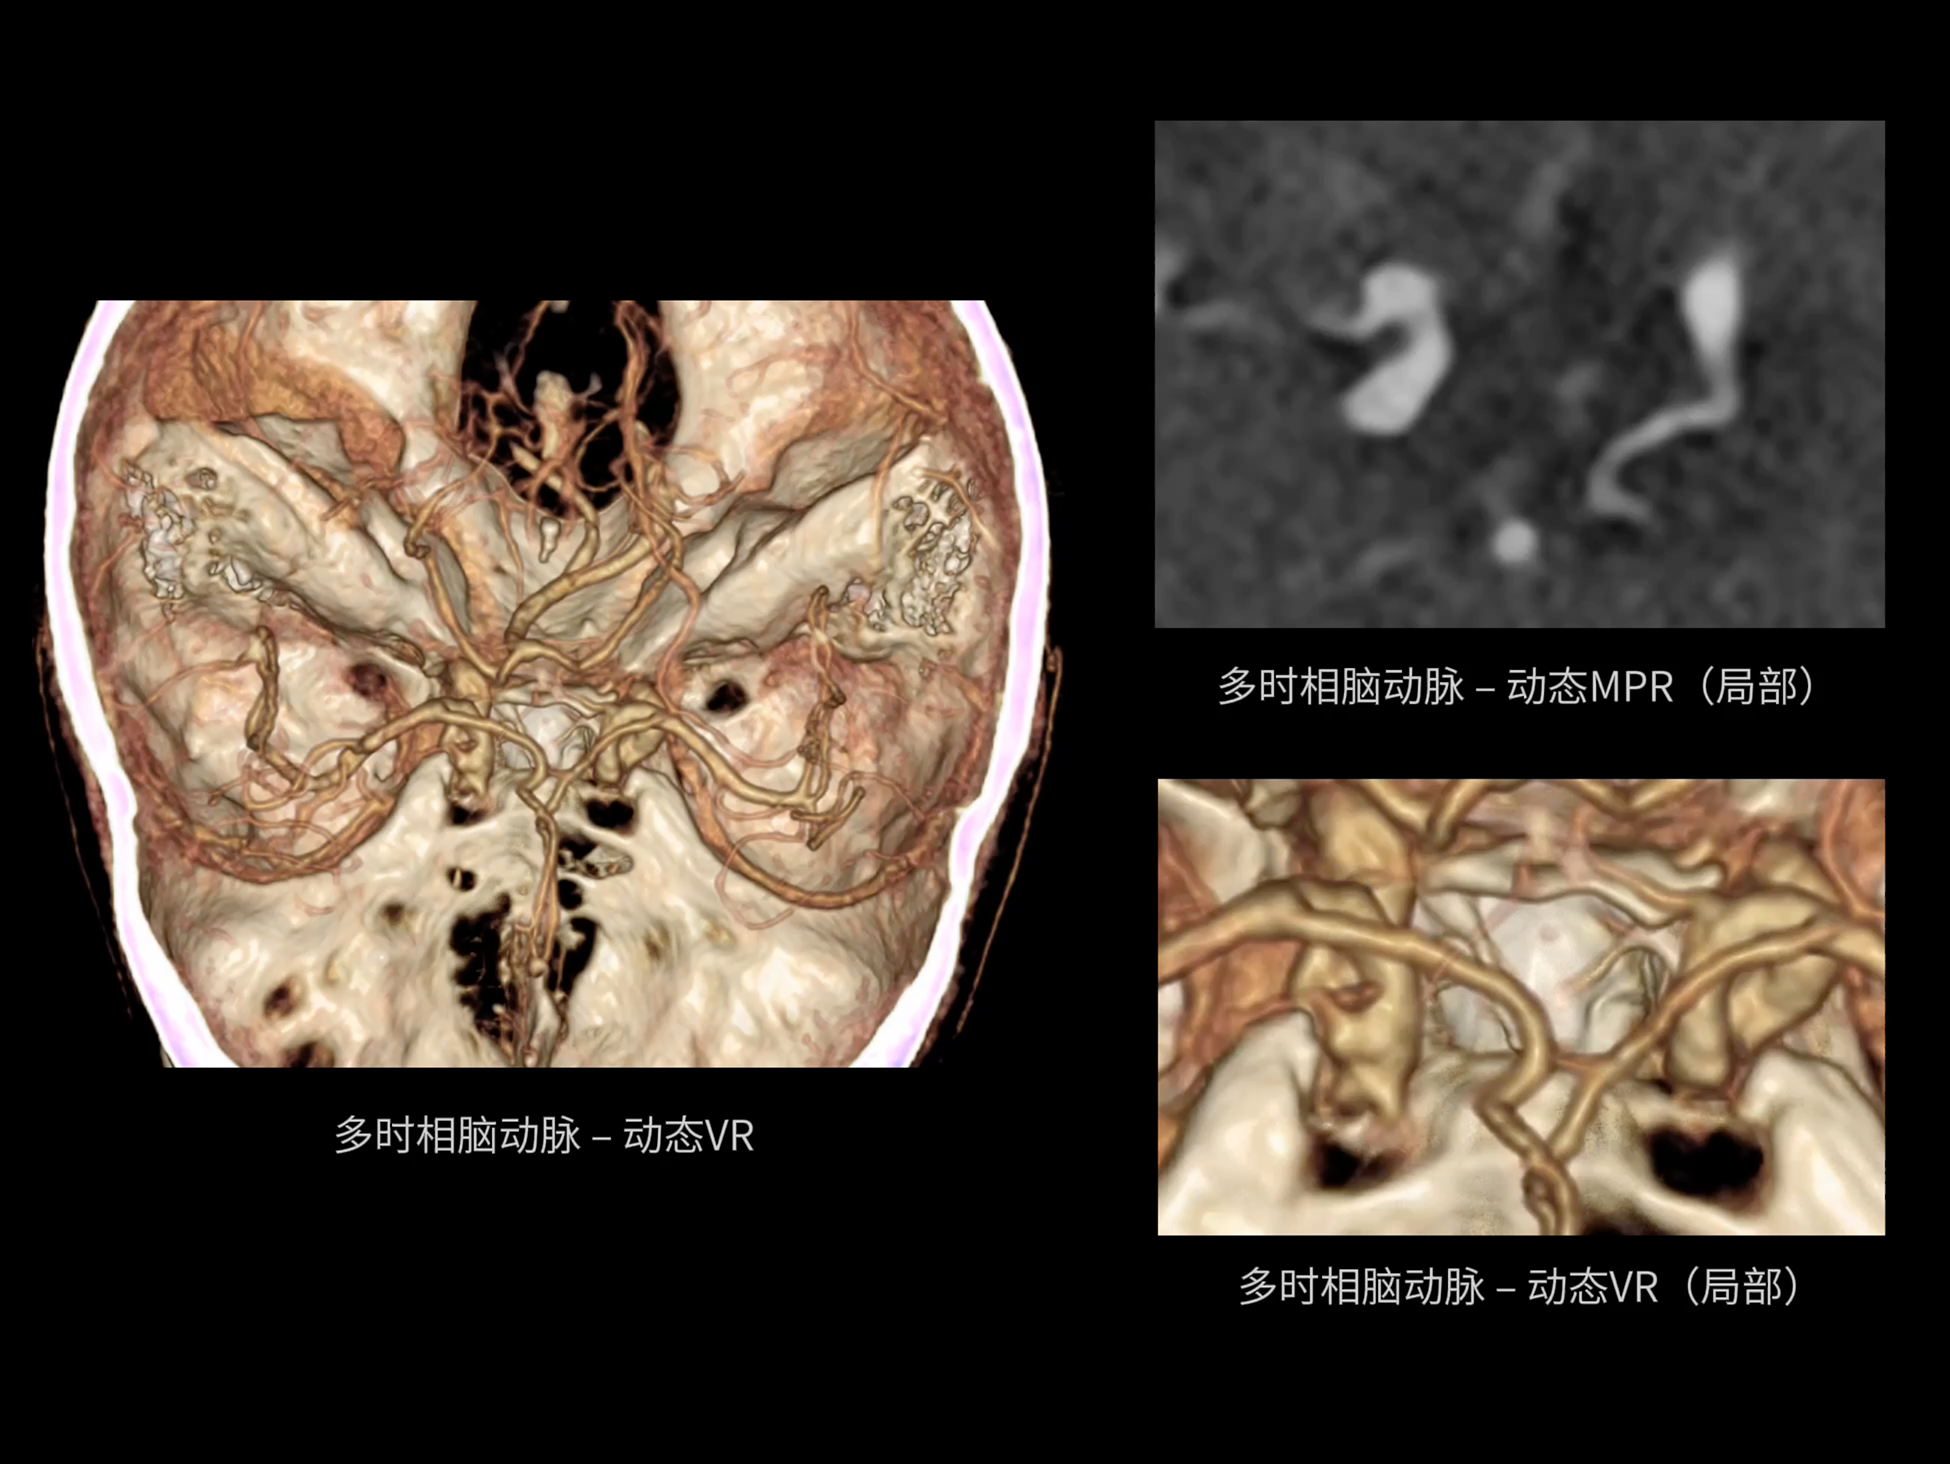

uCT SiriuX® 以全新双宽体系统架构,同步实现超高时间分辨率与宽体容积覆盖兼得,全面释放性能潜能,敏锐捕捉人体生理运动全景,带来动态影像新视角。

巅峰系统形态

双宽体“零”噪声时空探测器,Z 方向覆盖达16 cm,单圈即可完整扫描头颅、心脏等关键器官,结合超高时间分辨率,可实现真正意义上的全身各部位高清动态成像,让每一次扫描都更高效、更精准。

uCT SiriuX® 以16cm超宽Z轴覆盖,使超高时间分辨率应用于完整器官成像。无论是心脏搏动还是关节运动,整个目标区域可在同一瞬时被完整、清晰地捕捉,彻底消除时序误差,实现从“局部瞬间”到“全器官瞬时”的成像跨越。

全身各部位动态CT成像